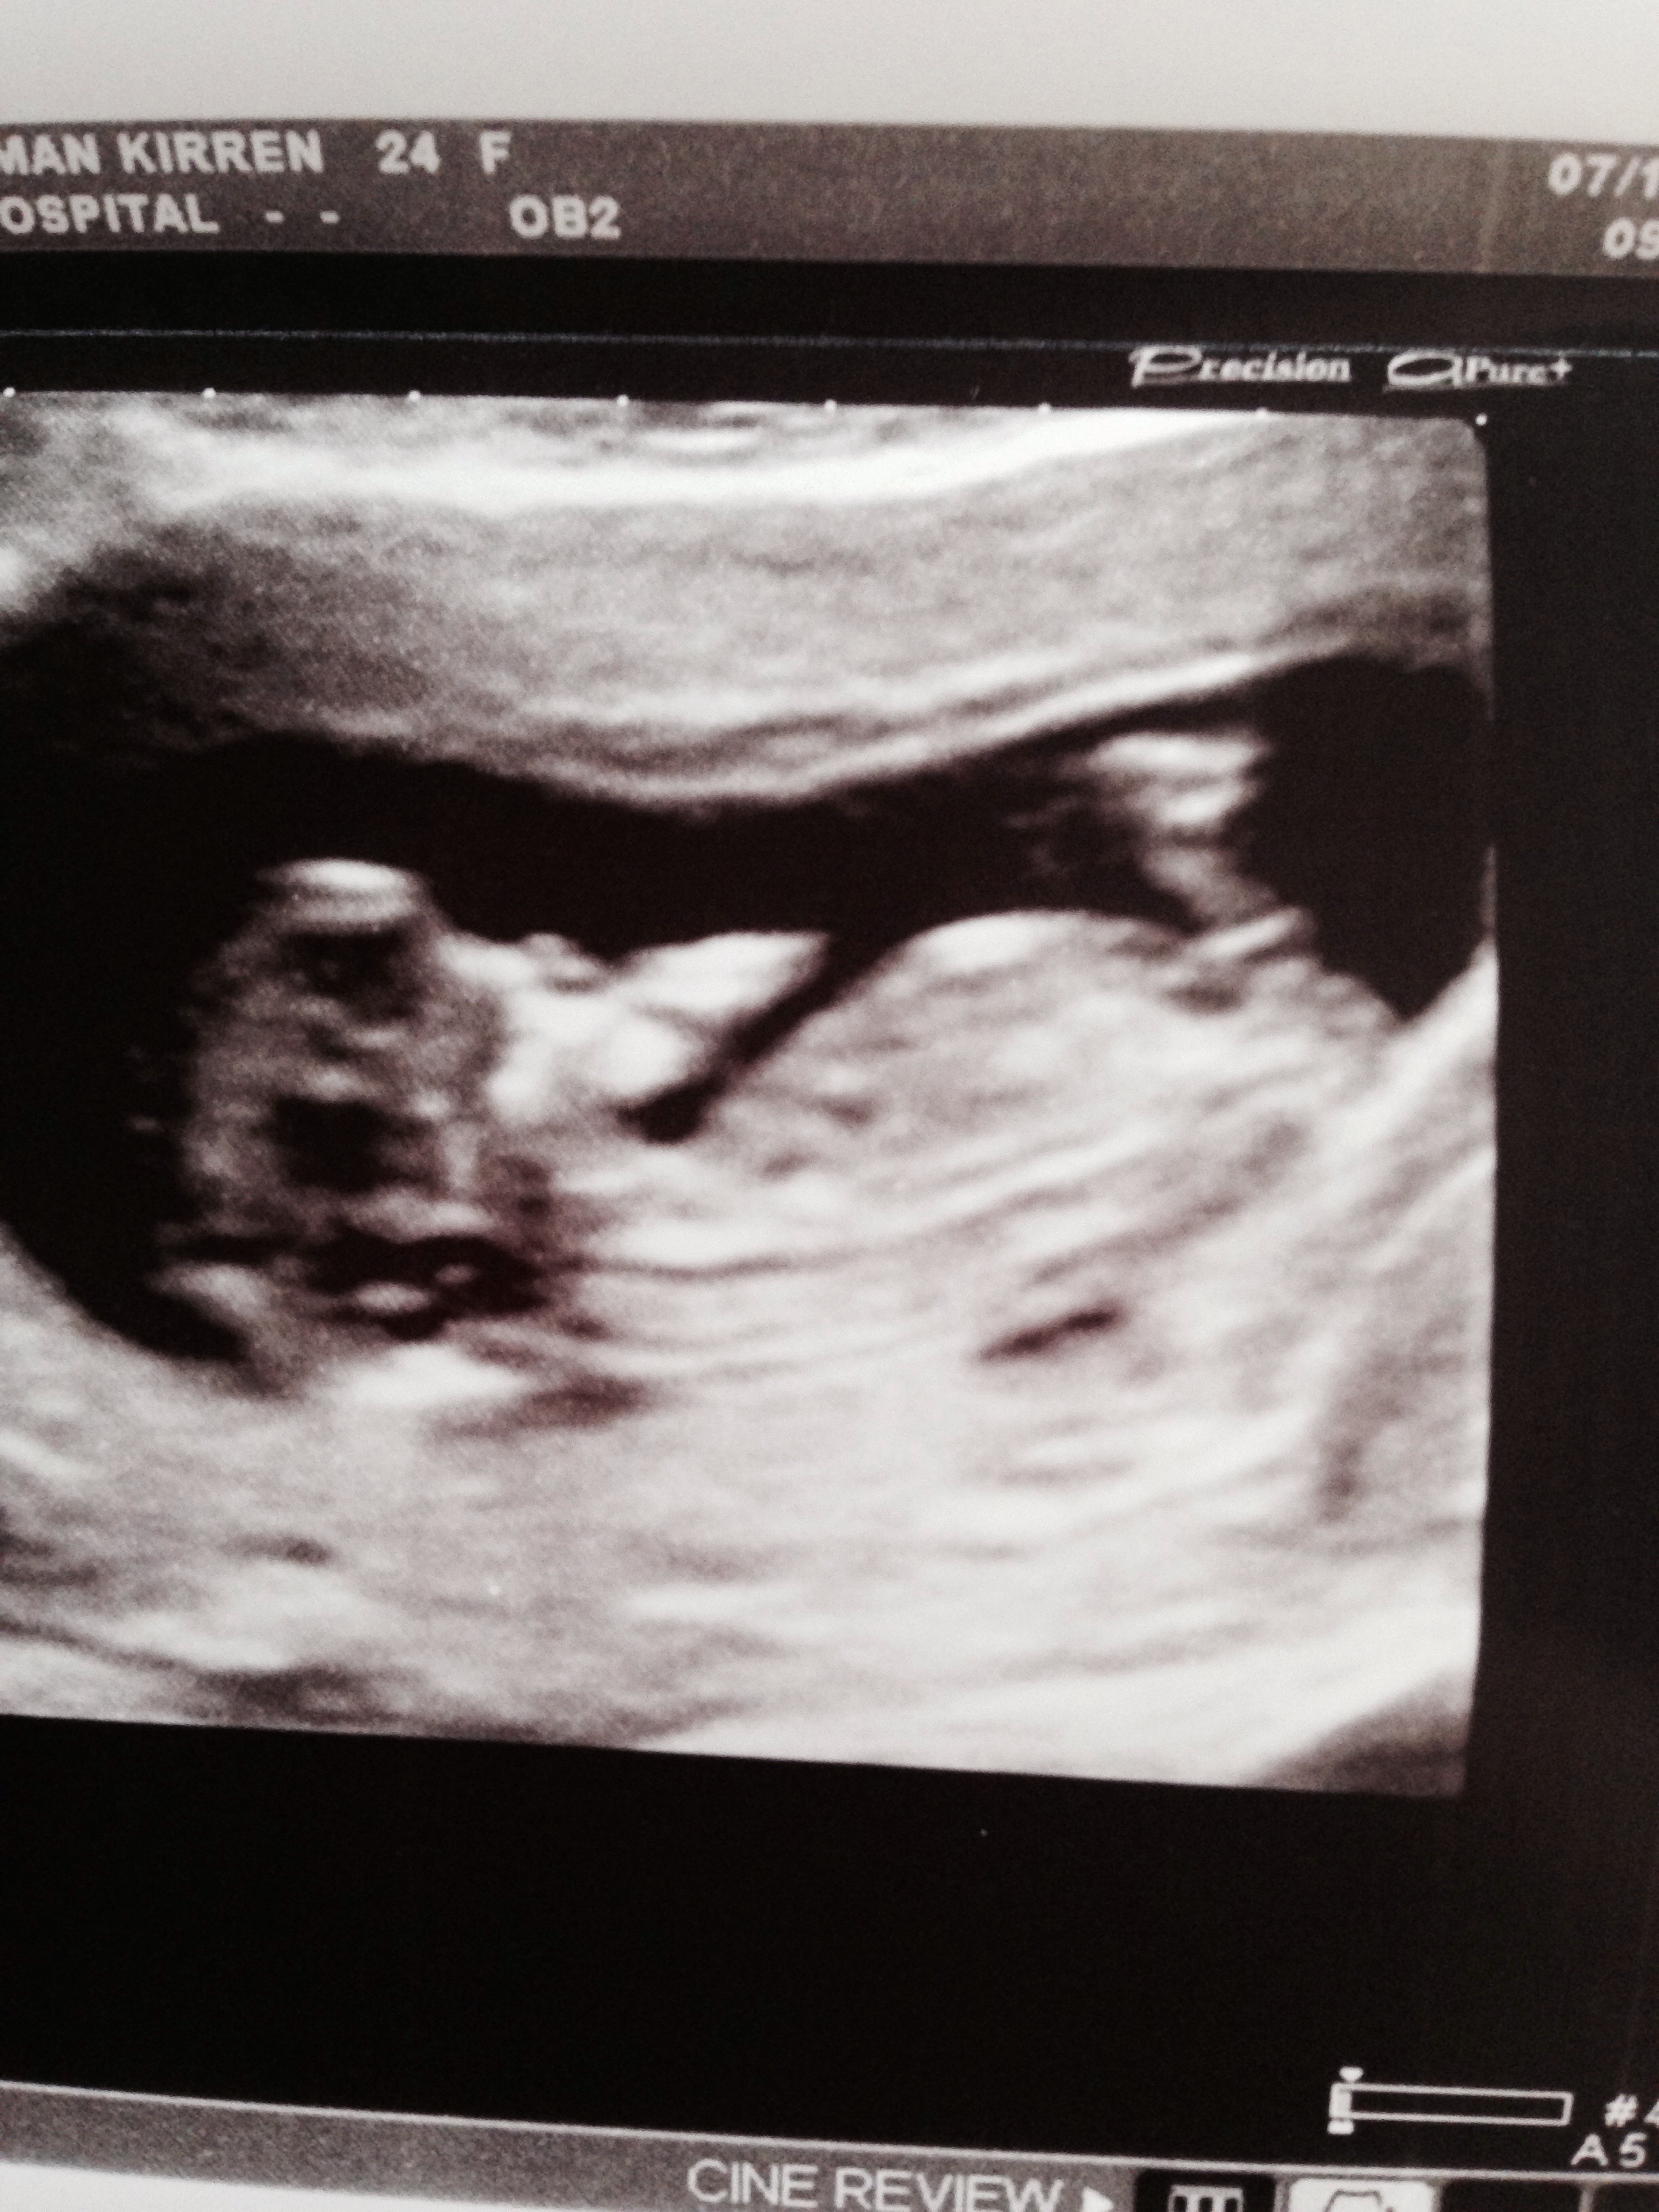

12weeks exactly girl or boy xAttachment 21335Attachment 21336

Still early but looks girly.

Looks stacked?.. Maybe boy

What does stacked mean? At the live scan it was a long forked pointing very flat nub

12 weeks exactly is pretty early, so it could still rise. I'd give a 65% chance for a girl.

Looks girly. Nubs can rise until the mid 12th week.